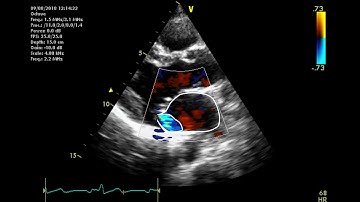

How to Localize Mitral Valve Pathology on 2D and 3D ECHO-A Quick and Easy Guide!